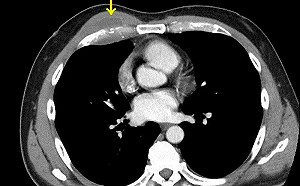

愛吃未熟雞蛋惹禍!罕見沙門氏菌感染致胸腔長膿瘍